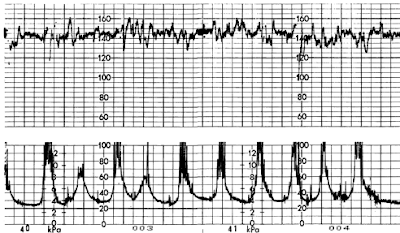

PHÂN TÍCH CƠN CO TỬ CUNG

+ các tiêu chí phân tích cơn co tử cung

- Trương lực cơ bản: khoảng 5 - 20mmHg

- Cường độ cơn co toàn bộ: khoảng 35 - 80mmHg

- Cường độ thật của cơn co: cường độ toàn bộ trừ đi trương lực cơ bản

- Tần số cơn co: số cơn co trong 10 phút, khoảng 3 - 5 cơn co.

- Thời gian cơn co: từ vài chục đến 80 giây

Sơ đồ cơn co tử cung